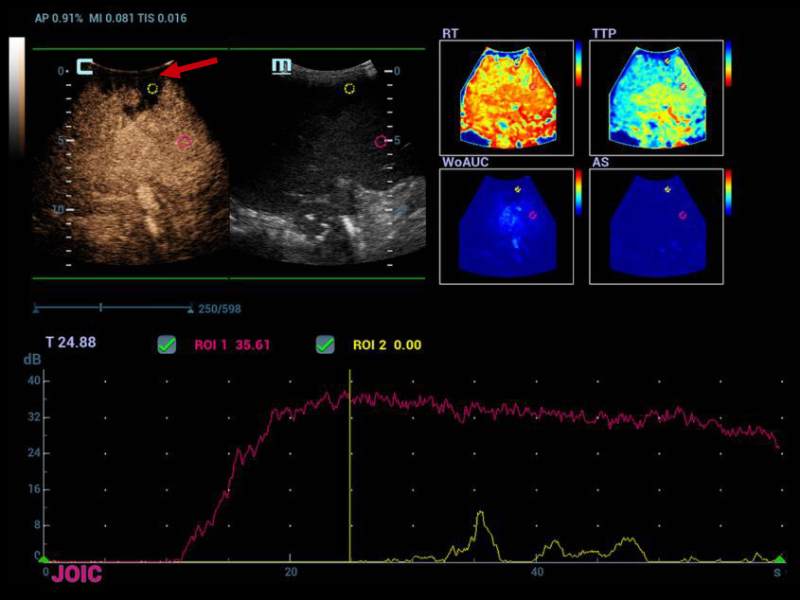

Therefore, it was decided to continue the assessment with contrasted ultrasound, an enhancement of vascular structures (Figures 2 and 3) can be observed about 8 seconds from the hepatic artery and 17 seconds from the portal vein without finding filling defects or areas of stenosis, however, in the portal phase of hepatic enhancement an area of hypoperfusion in segments 7/8, evidenced both by the live image and in the post-process of the perfusion curves and maps, this area was triangular morphology and subcapsular location (Figure 4), as well as the right hepatic artery is not visualized by this method, and the left was located at the level of the portal "H"(Figure 5).

Hypoperfusion zone in segment 8/7 in wedge morphology (red arrow), in the perfusion curves the ROI located in that segment does not show an enhancement of

Figure 4. Hypoperfusion zone in segment 8/7 in wedge morphology (red arrow), in the perfusion curves the ROI located in that segment does not show an enhancement of